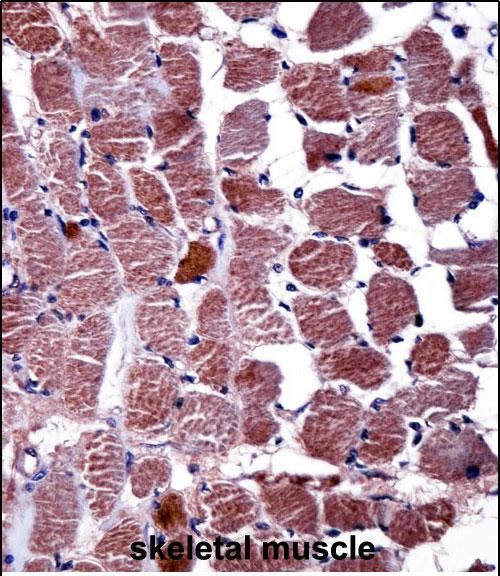

| IHC | 1/100-1/500 | Human,Mouse,Rat |

This antibody is commonly used in techniques like Western blotting, immunohistochemistry, or immunofluorescence to study RGS9 expression, localization, and protein interactions in tissues or cell lines. It has been instrumental in exploring neurological and visual disorders, including addiction, Parkinson’s disease, and retinal degenerative conditions. Researchers also utilize it to investigate RGS9’s role in GPCR desensitization and its therapeutic potential as a drug target. Specific validation for species reactivity (e.g., human, mouse, rat) and application-specific optimization is typically required for experimental accuracy.